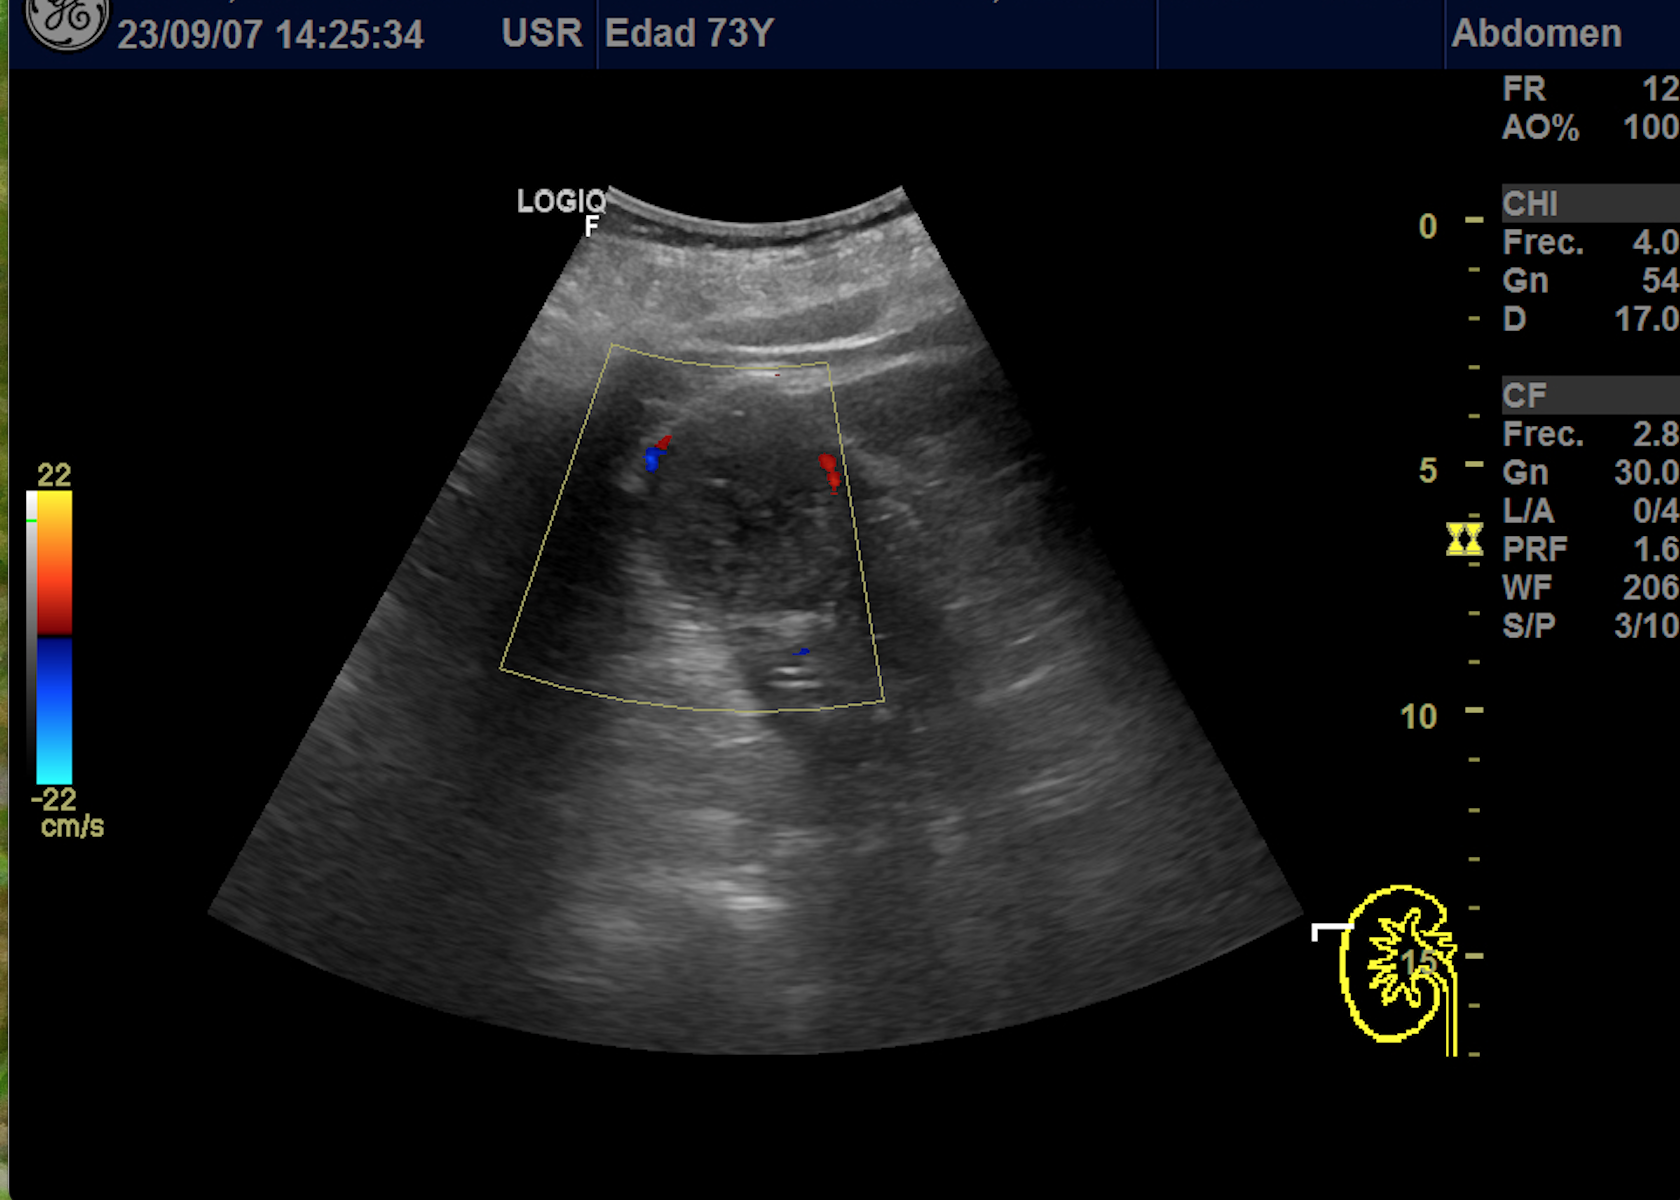

Hallazgos ecográficos

En polo superior de riñón derecho se observa una imagen redondeada, bien delimitada, isoecoica con un área central hipoecoica con vascularización periférica y central de 4,1 x 4,18 x 4,94 cm.

Riñon izquierdo sin hallazgos.